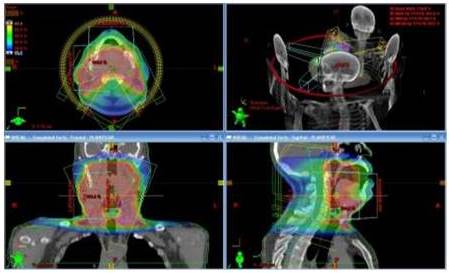

RAVM es la técnica primariamente usada para este tipo de lesiones. Se usan Rayos X de 6 MV y el paciente se posiciona decúbito supino. En el caso de que se deban tratar ambos hemi-cuellos se emplean 2 arcos axiales (camilla en 0°) parciales con ángulos de inicio y finalización de 150° y 210° para de esta manera minimizar la dosis en la médula espinal. En caso de que el tratamiento requiera la irradiación de un solo hemi-cuello, se usan 2 arcos axiales parciales de menor amplitud para así disminuir la dosis en estructuras que no son parte del PTV. En el caso de lesiones como las de senos paranasales y en aquellas donde no se necesite el tratamiento de ganglios linfáticos, se aplican arcos sagitales (camilla en 90° o 270°) obteniéndose distribuciones de dosis que favorecen la protección de estructuras como nervios ópticos, quiasma y ojos. El tiempo de tratamiento usando RAVM en estos casos es de alrededor de 3 min a diferencia de RTIM que toma alrededor de 20 min.

En la Figura 8 se muestra la distribución de dosis en plano axial, coronal y sagital del plan de un tratamiento de un cáncer en orofaringe, además de una vista tridimensional de la disposición de los arcos.